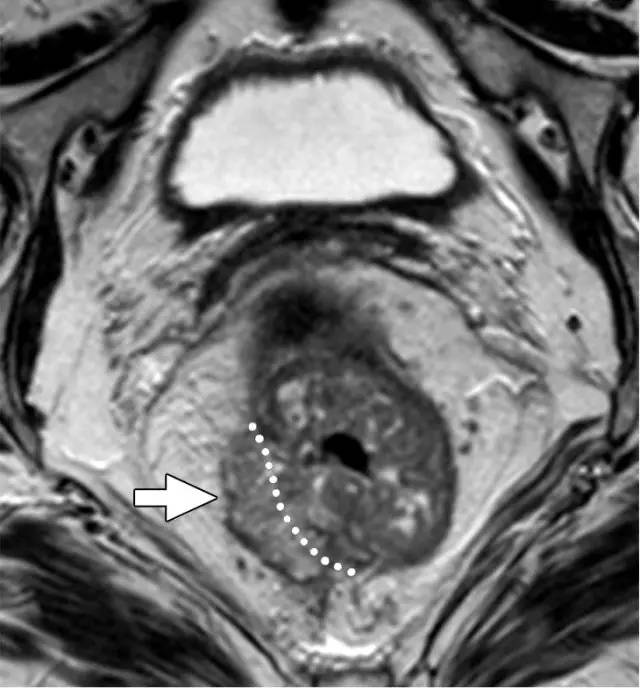

图 31 轴向 T2 加权图像报告 CRM 的距离。T3d 肿瘤局限于固有肌层内,肿瘤毗邻直肠系膜筋膜(箭头;肿瘤为 T2)。侵犯边界似乎是左后方(白色箭头),肿瘤的 CRM 评估为 5 mm。但有两个混合信号强度淋巴结(黑色箭头)邻接直肠,导致 CRM 为 0 mm。